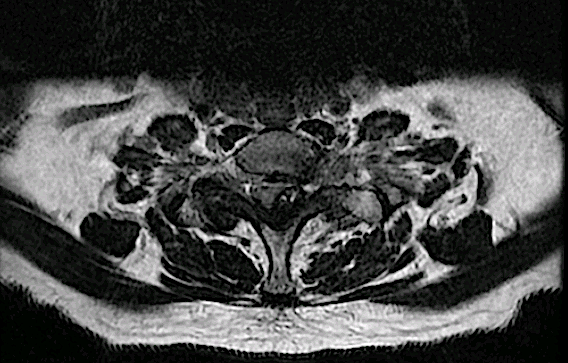

RM postoperatoria

Rm 6 meses

Corte axial C7-Th1